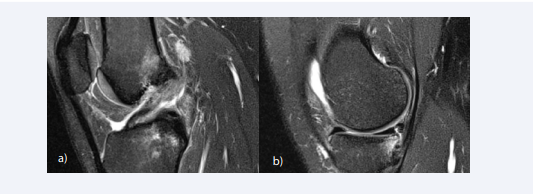

The ACL can undergo mucoid degeneration or intrasubstance ganglion cyst formation mimicking tear [78]. Mucoid degeneration of the ACL manifests as a thickened and ill-defined ligament with increased signal intensity interspersed among visible intact fibers on MRI (“celery stalk” sign) [79], which results from the deposition of amorphous mucoid matrix along the fibers of the ACL (Figure 6A).

Imaging pitfalls in diagnosing ACL tears. (A) The ACL is thickened and ill-defined with increased signal intensity interspersed among visible intact fibers on  sagittal T2-weighted image(“celery stalk” sign), resulting from mucoid degeneration of the ACL. (B) A fusiform, lobulated lesion with fluid-equivalent signal intensity  is noted interspersed within the ACL fibers. A ganglion cyst may be mistaken for a torn ACL.

Figure 6: Imaging pitfalls in diagnosing ACL tears. (A) The ACL is thickened and ill-defined with increased signal intensity interspersed among visible intact fibers on sagittal T2-weighted image(“celery stalk” sign), resulting from mucoid degeneration of the ACL. (B) A fusiform, lobulated lesion with fluid-equivalent signal intensity is noted interspersed within the ACL fibers. A ganglion cyst may be mistaken for a torn ACL.

Ganglion cysts appear as a fusiform, lobulated or multilobulated lesion with fluid-equivalent signal intensity on all pulse sequences [80]. Ganglion cysts are typically located along the course of the ACL, either interspersed within the ligament fibers or surrounding the ligament (Figure 6B). It is important to make sure that the ACL bundles are intact from origin to insertion, when making the diagnosis of mucoid degeneration or ACL ganglia, to exclude partial tears.